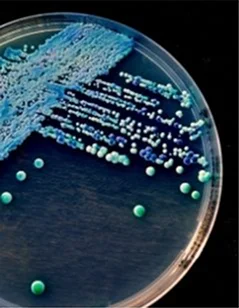

When bacteria enter the urinary tract through the urethra, it can lead to a Urinary Tract Infection (UTI) by spreading to the bladder. Although the urinary system is designed to prevent bacteria from entering, it may fail, resulting in an infection.

Women are more prone to UTIs, which typically affect the bladder or urethra. The infection is usually caused by Escherichia Coli, a bacteria commonly found in the gastrointestinal tract. However, other types of bacteria can also lead to UTIs.